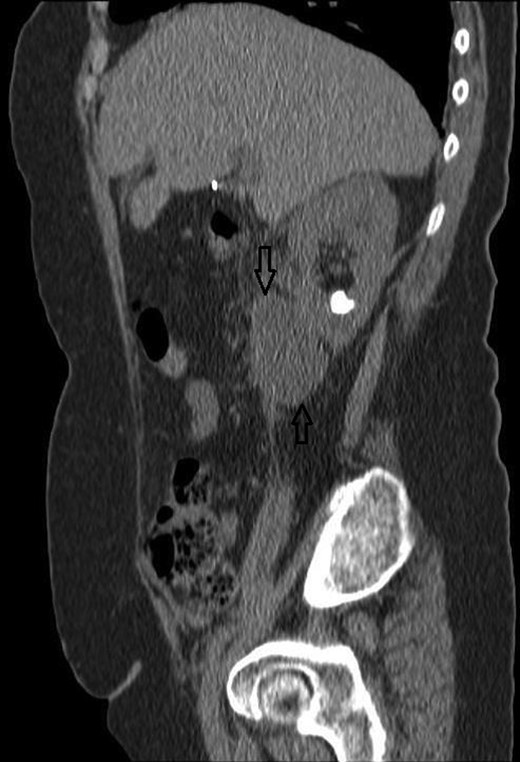

Despite intravenous antibiotics, after 72 h, the patient reported ongoing right loin pain and with persistently raised WCC at 16.6. A decision was made to proceed with a computerized tomography (CT) scan. This showed a bi-limbed right lower pole staghorn calculus measuring 29 × 16 mm associated with a 53 × 56 × 33 mm fluid collection within the right perinephric space. This was associated with inflammatory stranding abutting the lower pole in keeping with a urinoma secondary to a ruptured lower pole calyx, which was not dilated at the time of the scan (Figs 3 and 4).

A CT sagittal view, showing the calculus in the lower pole calyx and the collection below the kidney.